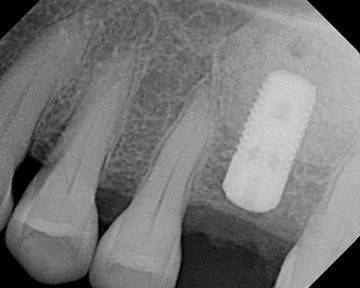

A sinus lift or sinus augmentation is a bone grafting procedure surgery that adds bone to your upper jaw in the area of your molars. Sinus Lift – Dental Treatment. The bone is added between your jaw and the maxillary sinuses in order to place a dental implant in areas were there is not enough bone structure to hold implants properly. As with other implant surgery , bone graft surgery can be performed under a local anesthetic.

Dental implants fuse with the jaw bone in a natural process called osseointegration, but this relies on there being a certain amount of bone present. The strength and integrity of a dental implant depend on the quality and quantity of bone used to anchor the implant. A minimum of 10mm of bone in this area is required to ensure long term success of an implant. Typically a sinus lift lateral window method is performed when there is less than 7mm of bone.